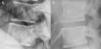

In imaging studies, in addition to marked bone sclerosis, her spine showed the presence of lines parallel to the cortex of the vertebral bodies giving rise to an image of a small copy of the vertebral body within the body, a sign called “bone within a bone” (Figs. 1–3). This sign was evident in several vertebral bodies. Morphometric vertebral deformities showed no calcification of paraspinal ligaments.